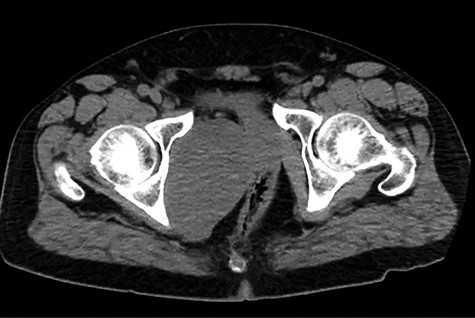

A healthy 47-year-old male with past medical history significant only for hypertension and nephrolithiasis presented to Englewood Health Medical Center in October 2019 with right flank pain radiating to the pubis, hematuria, hard stool with straining and fifteen pound weight loss over 6 months. On physical examination, multiple café au lait spots, small neurofibromas on his trunk and arms and axillary and inguinal freckling were observed. On CT scan, he was found to have a 10.1-cm soft tissue mass in the right hemipelvis and a nephroureteral stent with a 3-mm stone in the proximal right ureter (Fig. 1). Further history revealed the patient had a known pelvic mass discovered on CT approximately 10 years prior (Fig. 2), which was again observed on CT in June 2019 during a hospitalization for nephrolithiasis at Hackensack University Medical Center (Fig. 3); he had been lost to follow-up.

HUMC 6/1/19: 9.7 × 6.3 × 7.5-cm-sized right pelvic wall soft tissue mass.